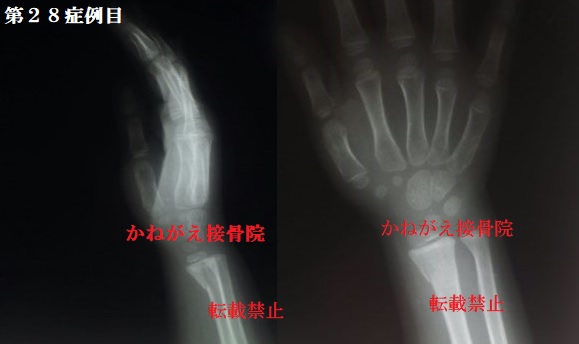

症例28

当時4歳 女性

右掌側バートン骨折

今回の症例はバートン骨折という関節の一部を巻

き込んだ骨折で、そのほとんどが手術での治療を

選択されています。

しかしこの患者さんは4歳で骨もまだまだできて

おらず、手術跡が大きく残る可能性や骨に金属を

打ち込む辛さ等を考えると、手術は回避してほし

いと思いました。

幸い、医師が整復可能だと判断したため徒手整復

にて保存的に治療をすることになりました。

受傷翌日の来院でしたが、骨折の症状は

限局性圧痛(+)、腫脹(+)、皮下出血(+)

神経・大血管損傷(−)、皮膚損傷(−)

転位(+)→橈屈(+)、橈側(+)

掌屈(+)、掌側(+)

特筆すべき持病などはなし

だったので整復しました。

結果から言うと、「Repo perfect」 でした。                   画質が悪いですが、折れている場所がわからない 位にきれいに整復できているのが確認できるかと 思います。                  この患者さんは整復の時に大泣きしていましたが 何とかキレイに戻す事ができました。      回復も早く、固定後1ヶ月ほどで完治されました 学齢期前のお子さんの場合、意思疎通が難しい場 合があり本気で整復を嫌がりますが、様々な工夫 や親御さんの協力を得る事で骨を引っ張ることが 出来ます。                  手術をしないで治すために、ご理解とご協力いた だける事に感謝しながら、さらに安定的に的確な 整復ができるように頑張ろうと思った症例でした 以上、第28症例目の整復レポートでした。